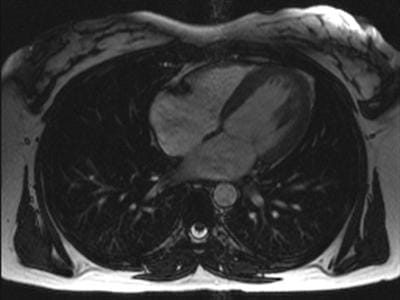

Η μαγνητική τομογραφία καρδιάς (Cardiac MRI) αποτελεί μία από τις πλέον σύγχρονες και αξιόπιστες απεικονιστικές μεθόδους για την αξιολόγηση της καρδιάς και των μεγάλων αγγείων, χωρίς τη χρήση ιονίζουσας ακτινοβολίας. Προσφέρει τρισδιάστατη απεικόνιση υψηλής ανάλυσης και παρέχει κρίσιμες πληροφορίες για τη δομή και λειτουργία του μυοκαρδίου.

Η εξέταση αξιολογείται από τον Δρ. Μάριο Ματιάκη, καρδιολόγο με εξειδίκευση στη Μαγνητική Τομογραφία Καρδιάς στο Πανεπιστημιακό Νοσοκομείο Charité Βερολίνου, με πολυετή εμπειρία στον τομέα της καρδιακής απεικόνισης και της διαστρωμάτωσης κινδύνου. Η μαγνητική καρδιάς πραγματοποιείται κατόπιν ραντεβού και αποτελεί αναπόσπαστο εργαλείο στη σύγχρονη διαγνωστική καρδιολογία.